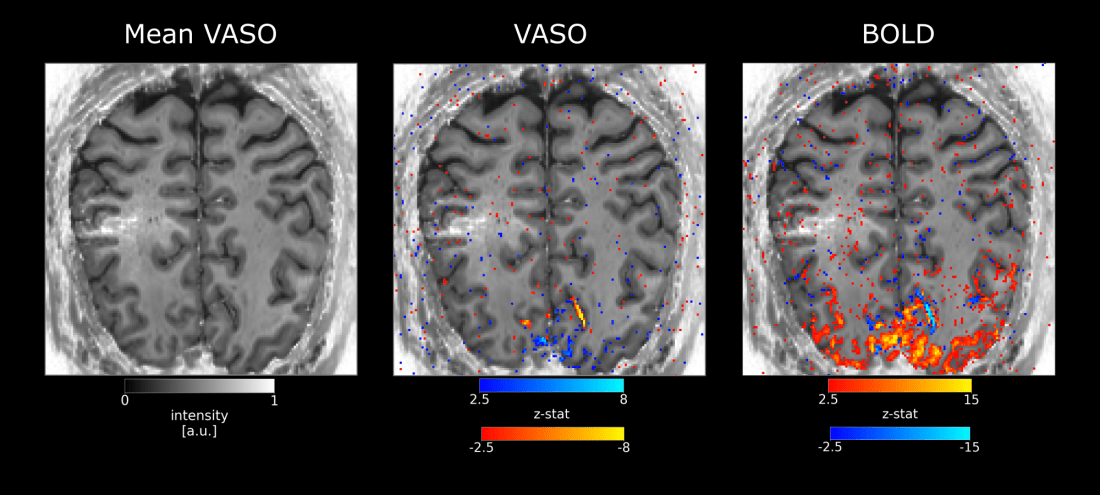

BOLD and VASO results in visual cortex. -

Alternating BOLD and VASO maps from MGH